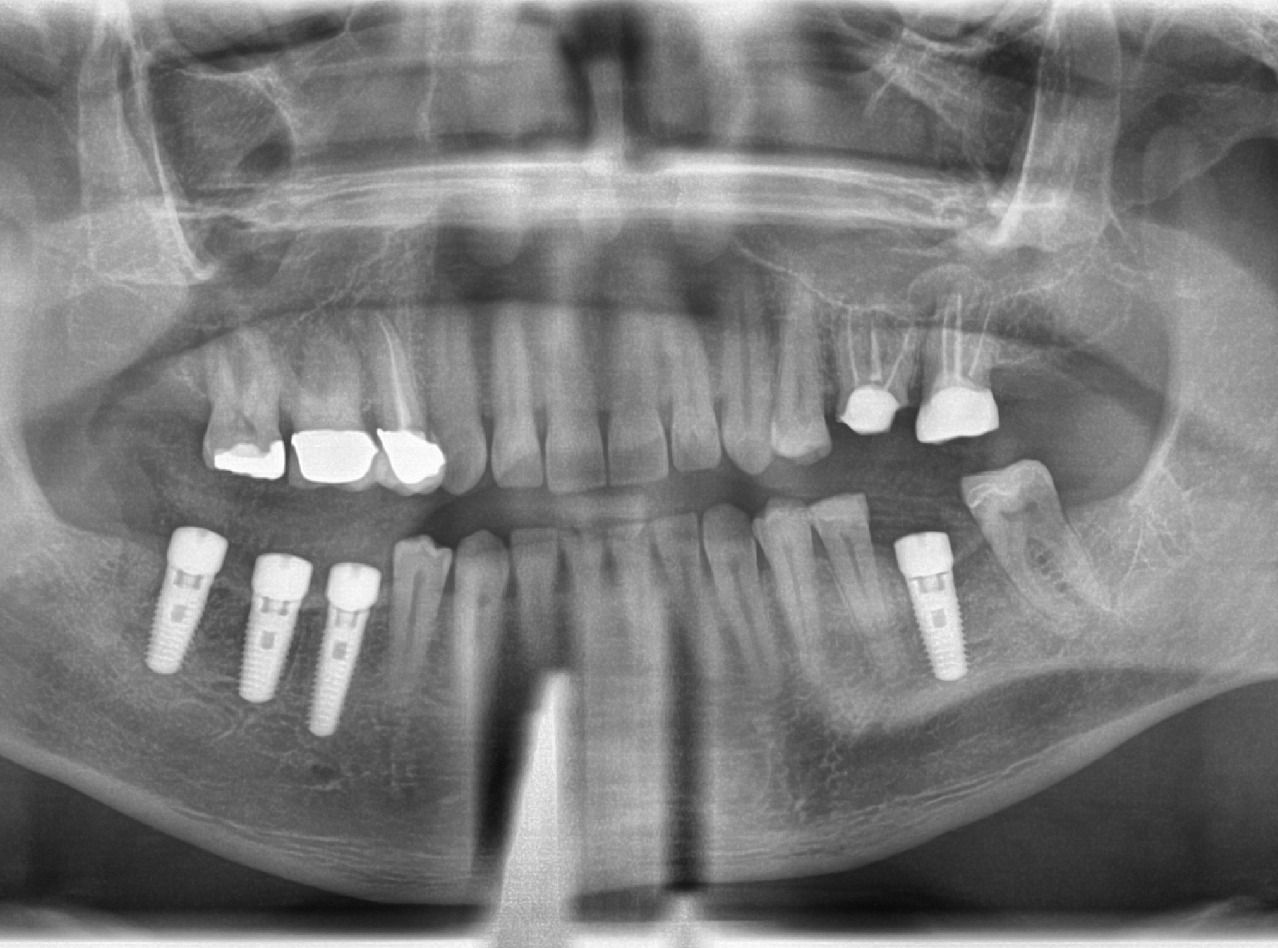

A csapatunkat magasan képzett, tapasztalt fogorvosok, dentálhigiénikusok és asszisztensek alkotják, akik elkötelezettek az innováció és a kiválóság mellett. Szolgáltatásaink közé tartozik a fogtömés, gyökérkezelés, fogpótlás, implántátumbeültetés, fogfehérítés, ultrahangos fogkőeltávolítás és személyre szabott esztétikai kezelések direkt héjak segítségével.

Szolgáltatásaink közé tartozik a precíz fogkoronák, foghidak, gyökérkezelések, bölcsességfog eltávolítás, héjak, és kivehető fogsorok készítése. Emellett kiemelt figyelmet fordítunk a szájhigiéniai kezelésekre, a fogínybetegségek kezelésére, és a komplex fogászati sebészeti beavatkozásokra.